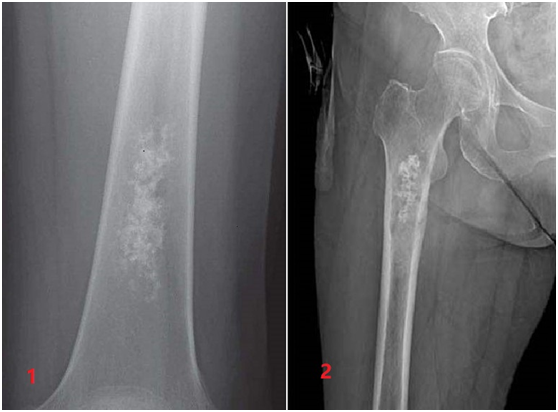

软骨肉瘤表现为皮质膨胀、侵蚀、破坏,病变界限不清,边缘模糊,呈云絮状密度(图1)。内生软骨瘤表现为边界清楚的髓腔内圆形或卵圆形病灶,密度不均,呈爆米花样,见矿化点,无皮质膨胀、增厚、破坏及软组织包块(图2)。